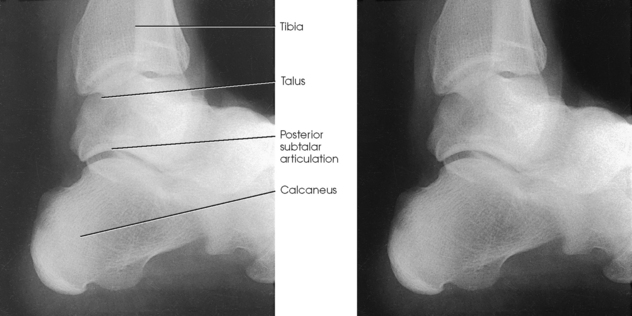

Structures shown: The resulting image shows a true lateral projection of the lower third of the tibia and fibula; the ankle joint; and the tarsals, including the base of the fifth metatarsal (Figs. 6-94 and 6-95).

Fig. 6-94 Bones shown on lateral ankle. Including base of fifth metatarsal on lateral ankle projection can identify Jones fracture if present.